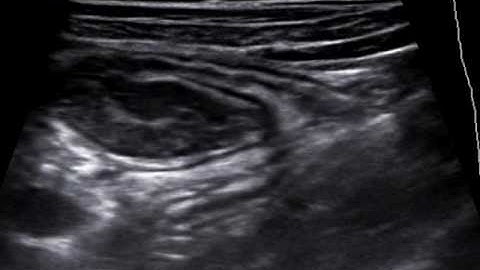

Intussusception Video